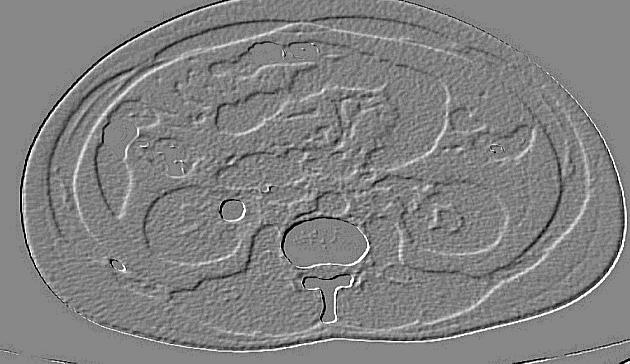

Fig6 CTexaminedpictures

Bringinginthepicturethroughpicturesecuringapparatuses;Breakingdownandcontrollingthepicture;Outputin whichresultcanbeadjustedpicture.

ImagePre processingisacommonnameforoperationswithimagesatthelowestlevelofabstraction.Itsinputand outputareintensityimages.

The point of pre handling is an improvement of the picture information that stifles undesirable contortions or upgrades somepicturehighlightssignificantforfurtherprocessing.